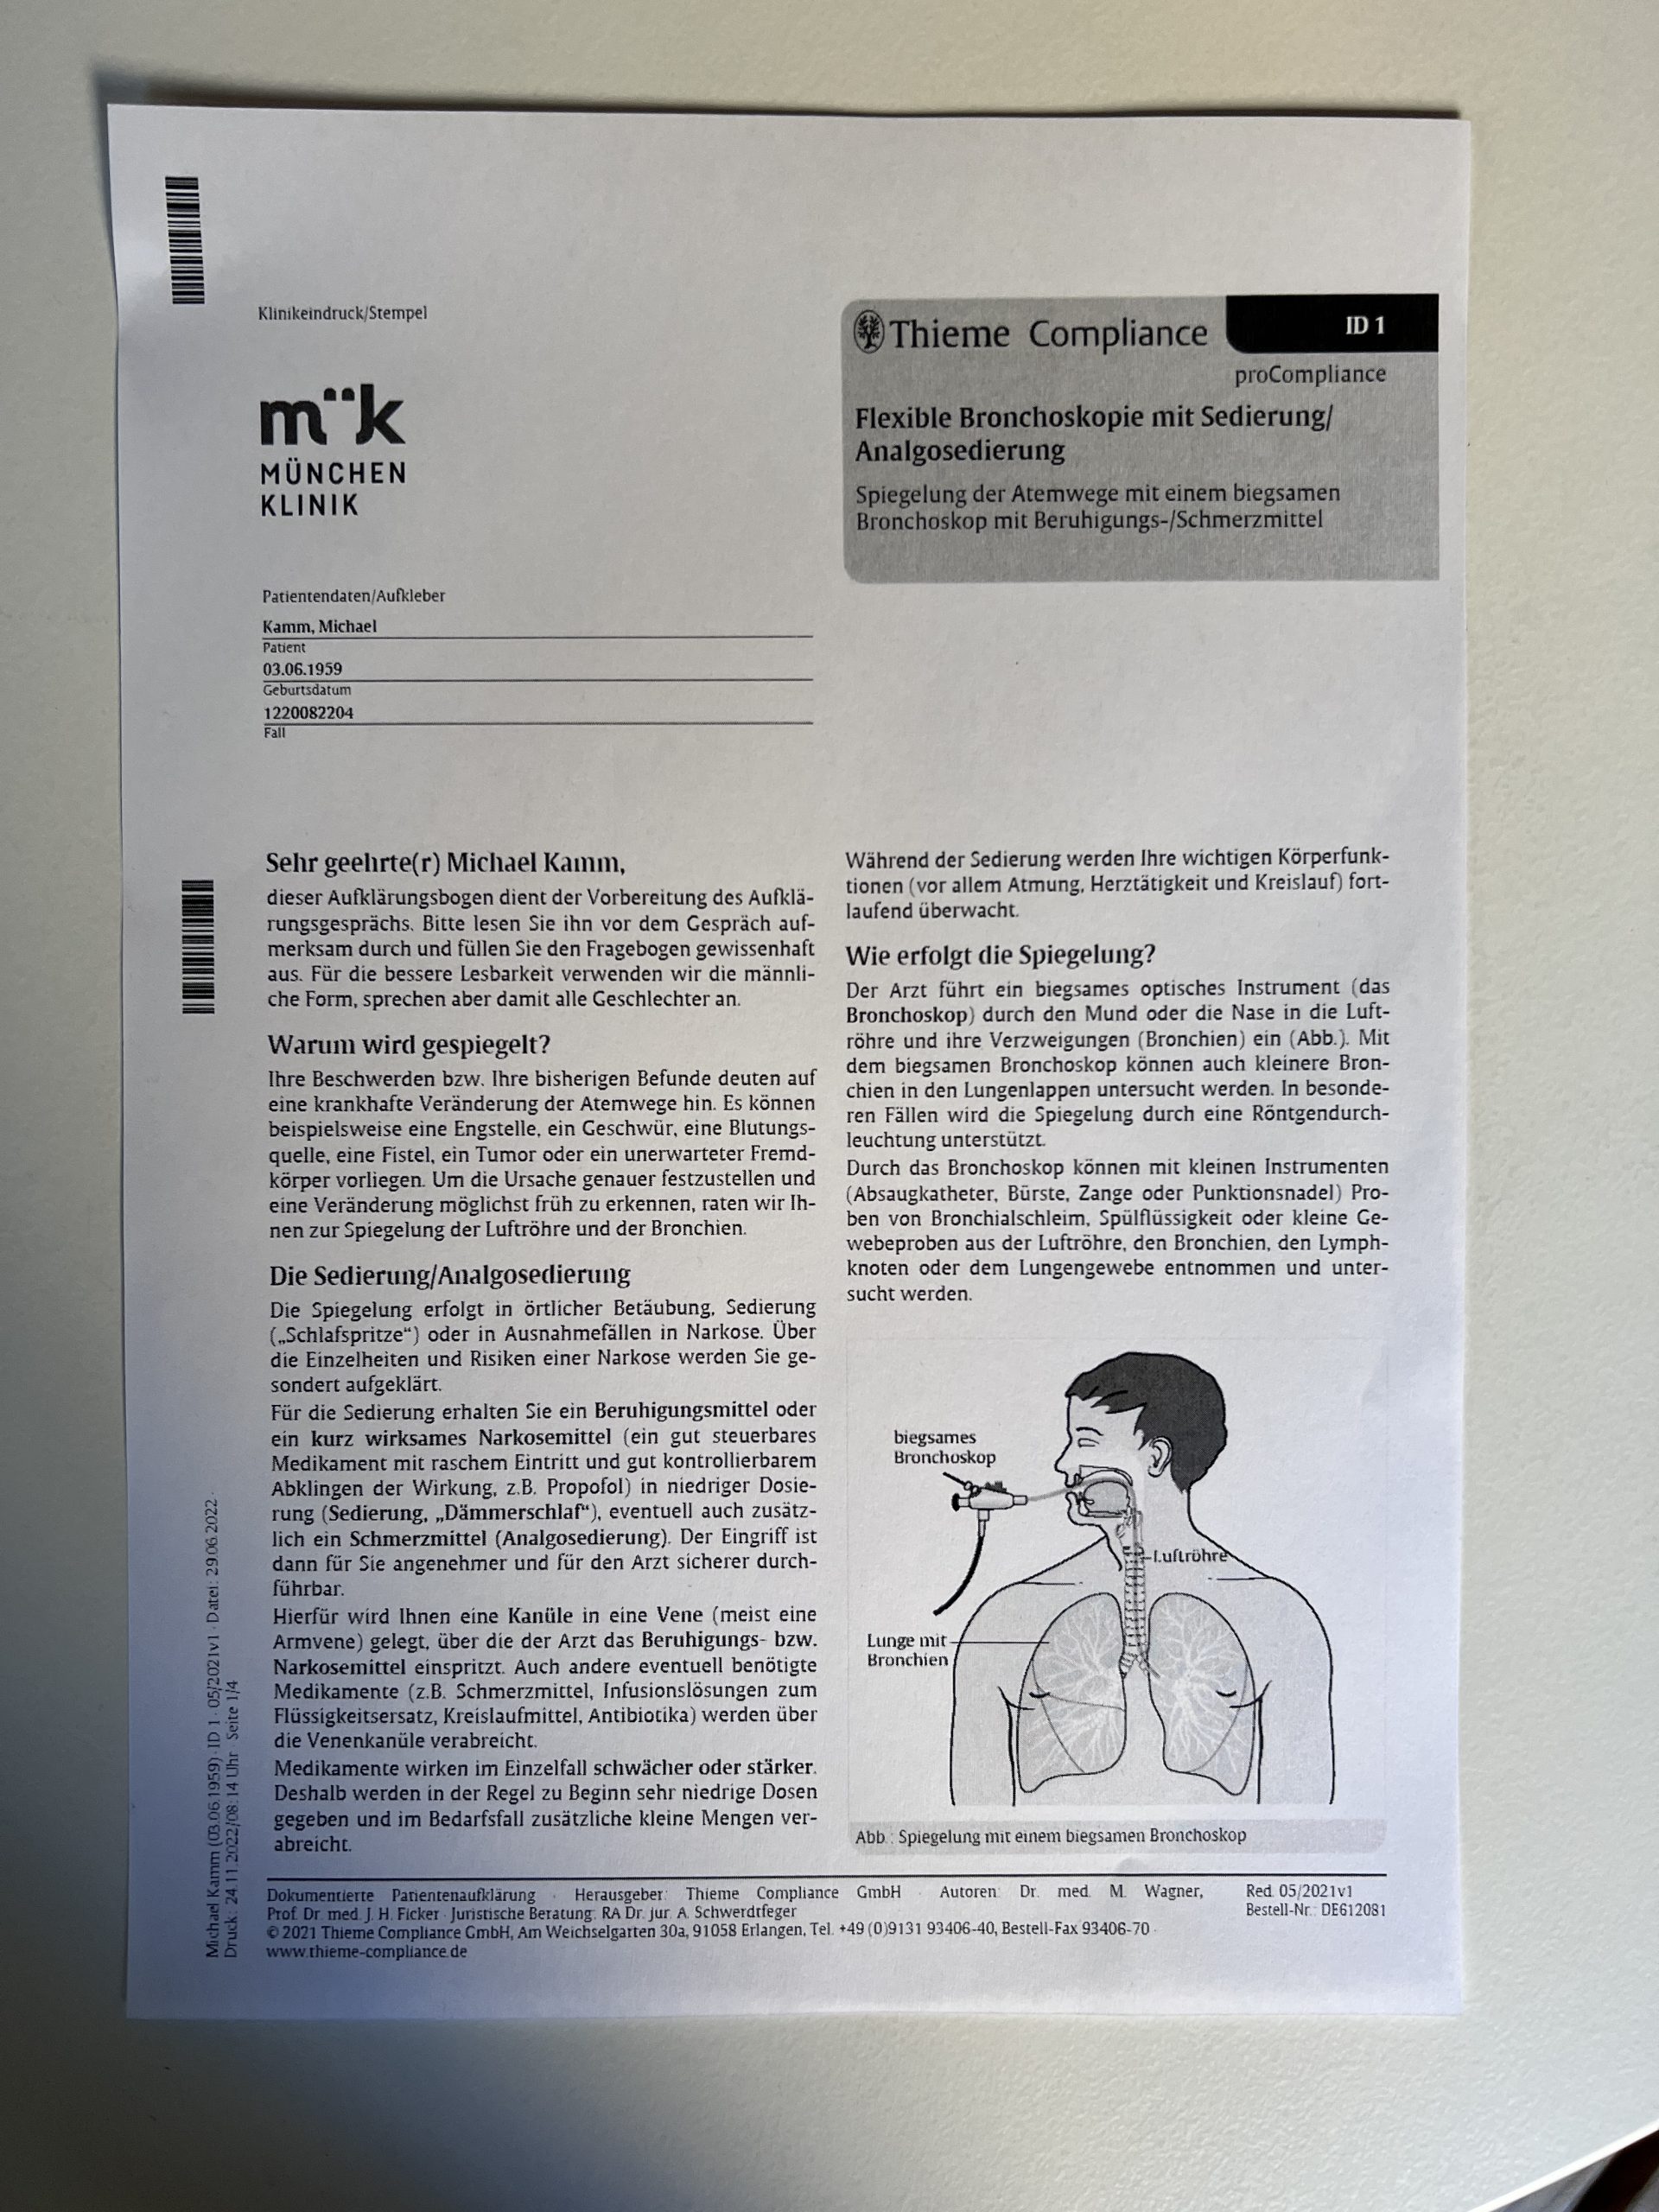

Eine leider festgestellte fortschreitende Veränderung meines Lungengerüsts durch eine Fibrose bedurfte Ende November einer exakten Diagnose der genauen Erkrankungsursache. Hierzu war eine Bronchioskopie mit Gewebeentnahme im Rahmen eines stationären Aufenthalts in einer Klinik notwendig. Erst auf Basis einer belastbaren Diagnostik ist die optimale Entscheidung eines Pneumologen bezüglich der Bestimmung einer passenden Therapie möglich. Nicht schön, aber unumgänglich. Ich entscheide mich aus rein praktikablen Gründen für das Bogenhausener Klinikum, da dieses städtische Krankenhaus nahe zu uns liegt und zudem über eine Lungenabteilung mit gutem Ruf verfügt. Die Lungenbiopsie zählt zu den diagnostischen Verfahren der Medizin. Sie hat vor allem im Bereich der Lungenheilkunde zur Gewinnung von Lungengewebe einen großen Stellenwert. Das mittels Lungenbiopsie gewonnene Gewebe kann einer Vielzahl an weiteren Untersuchungen unterzogen werden, beispielsweise histologischen, zytologischen, immunologischen oder genetischen Tests. Die Lungenbiopsie gehört zu den invasiven Verfahren der Diagnostik. Sie kommt daher nur äußerst selten als erstes diagnostisches Verfahren zum Einsatz. Prinzipiell sollte jede Erkrankung des Lungengewebes, die sich durch klinische Symptome bemerkbar macht und mittels radiologischen Verfahren nachweisbar ist, mittels einer Lungenbiopsie weiter klassifiziert werden müssen. Erkrankungen des Lungengewebes umfassen dabei Veränderungen im Bereich der Lungengefäße, des Lungengewebes – dem Parenchym – selbst oder der Pleura. Biopsien im Inneren eines Lungenlappens sind im Rahmen einer Bronchoskopie entnehmbar: Nach Einführung des Bronchoskops über den Rachen und den Hals in den zu untersuchenden Lungenflügel wird das zu biopsierende Areal aufgesucht. Mittels einer Biopsiezange - in meinem Fall war es eine vereiste Metallspitze - wird ein Stück des Lungengewebes gefasst, herausgetrennt und durch das Bronchoskop herausgezogen. Als Komplikation kann eine Blutung des biopsierten Lungengewebes auftreten. Dieses Verfahren hat von den oben genannten die geringste Invasivität, da keine Körperhöhlen eröffnet werden. Es kann auch bei gesundheitlich schwer angeschlagenen Patienten verwendet werden. Biopsien mittels Thorakoskopie müssen im Operationssaal unter sterilen Bedingungen durchgeführt werden. In Lokalanästhesie wird durch einen kleinen Schnitt ein Thorakoskop in die Brusthöhle eingeführt und mit einer Biopsiezange Lungengewebe entnommen. Mit diesem Verfahren kann im Gegensatz zur bronchoskopisch durchgeführten Lungenbiopsie, nur peripheres, an der Lungenoberfläche gelegenes Gewebe entnommen werden. Neben einer möglichen Blutung im Bereich des Biopsieareals kann ein Pneumothorax oder eine Infektion des Gewebes als Komplikation auftreten.

Ganz ohne Risiken ist der Eingriff nicht ... die erschreckende Liste der möglichen Problemfelder sollte man sich nicht zu oft durchlesen, sonst könnte man dazu neigen wieder Abstand von dem Vorhaben zu nehmen